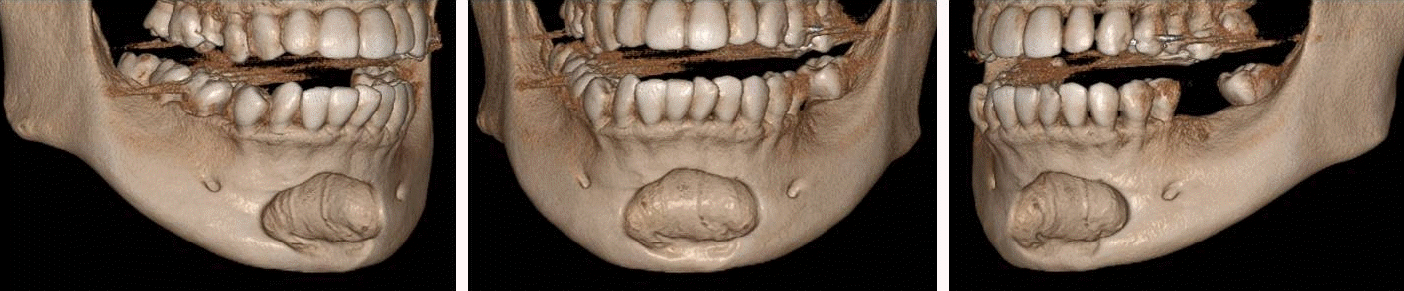

Figure 1.

Panoramic view. A well-defined, corticated, oval-shaped radiolucency was observed in the periapical region of the mandibular right to left first premolars on panoramic radiography.

32세 여성 환자의 파노라마방사선영상에서 하악 전치부 낭이 관찰되어, 정확한 진단을 위하여 본원에 의뢰되었다. 특별한 임상증상은 없었다. 파노라마방사선영상에서 하악 우측 제1소구치에서 좌측 제1소구치 치근하방에 경계가 명확하고 피질골성 변연을 가진 타원형의 방사선투과상이 관찰되었다(Fig. 1). 방사선투과상은 해당치아들과는 무관하여 치근단낭이 배제되었고, 단순골낭의 가능성을 염두에 두고 콘빔CT 검사를 시행하였다. 콘빔CT에서 중심성 골내 병소가 아닌 악골의 순측에서 설측으로 함몰된 변연성 병소가 관찰되었다(Fig. 2). 병소의 경계는 매우 평활하였고, 단면상에서는 넓은 접시모양처럼(Fig. 3), 악골 절단면상에서는 반달모양처럼 함몰되어 있었다(Fig. 4). 설측 피질골은 비박되어 있었으나 천공은 관찰되지 않았다. 함몰된 부위는 공기가 아닌 연조직의 방사선투과상으로 채워졌으나, 콘빔CT에서는 대조도가 낮아서 연조직간의 감별이 가능하지 않았다(Fig. 5). 관찰된 턱 끝 부위의 골 함몰이 해부학적 변이인지 아닌지를 감별하기 위하여 환자의 과거 병력을 알아보았다. 환자는 2년 전에 턱 끝 부위에 미용 필러 시술을 받았다고 하였다. 방사선영상소견과 문진결과를 토대로, 미용 필러와 관련된 골흡수를 의심하였다. 이후 외과적으로 미용 필러 제거와 함몰된 부위에 골이식이 시행되었다. 수술 중에 육안으로 남아있는 미용 필러와 작은 석회화 물질들이 확인되었다. 수술 후 생검에서 다핵거대세포와 결절석회화가 관찰되었고, 피부석회화(calcinosis cutis)가 의심된다는 결과를 받았다. 이상의 술 전 검사 및 술 후 소견을 종합하여, 파노라마방사선영상에서 관찰된 방사선투과상은 치성낭이나 해부학적 변이가 아니고 미용 필러에 의한 하악골 순측 골흡수로 최종 진단되었다.